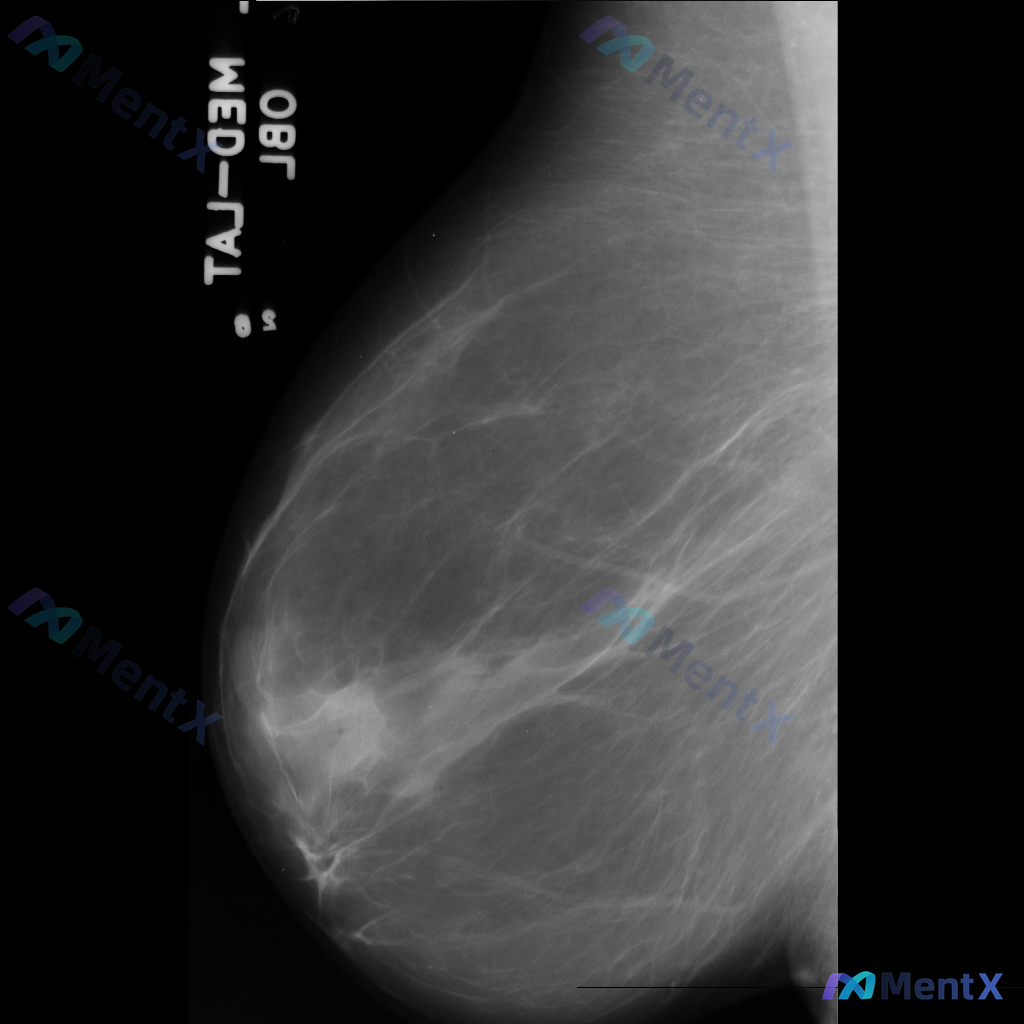

整理到一份乳腺钼靶影像资料,主要表现如下: - 乳腺中后部可见局灶性结构扭曲 - 无明确的肿块核心 - 周围腺体和脂肪界面被不规则牵拉 目前暂不提供既往影像对比和详细病史(手术史、外伤史、炎症史等)。 这种表现大家会先怎么判断?更倾向于往哪种方向考虑?

整理到一张乳腺钼靶影像的分析资料,大家可以先基于现有信息讨论一下。 基本影像学表现 - 可见形态不规则的致密区域,伴有结构扭曲和模糊边缘 - 背景乳腺腺体呈 BI-RADS B/C 型(致密性增加) 目前从影像上看,存在几种可能的方向,想听听大家的第一判断:单看这组影像学表现,你会先考虑哪一种异常方...